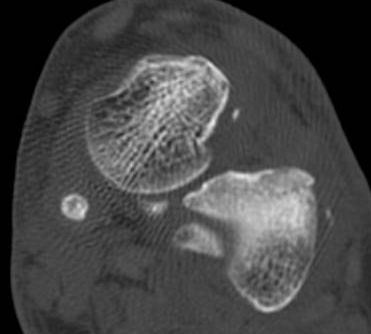

ÄÄÇ»ÅÍ ÃÔ¿µ : Á¾°ñÀÇ °ñÀý , µÎ ºÎÀ§(÷ºÎ ÆÄÀÏ Âü°í)

ÄÄÇ»ÅÍ ÃÔ¿µ ÆÇµ¶¿¡¼­ Á¾°ñÀÇ µÎ ºÎÀ§ °ß¿­°ñÀýÀÌ ¾ð±ÞµÇ¾úÁö¸¸ ÃÊÀ½ÆÄ°Ë»ç»ó  Ãß°¡ÀûÀÎ °ñÀýÀ»

È®ÀÎÇÒ ¼ö ÀÖ¾ú´Ù.

ÄÄÇ»ÅÍ ÃÔ¿­»óÀÇ °ñÀý ºÎÀ§´Â ÃÊÀ½ÆÄ°Ë»ç¿¡¼­ È®ÀÎÇÒ ¼ö ÀÖ¾ú°í »çÁø 10~15¿¡¼­ È®ÀÎÀÌ °¡´ÉÇÏ´Ù.